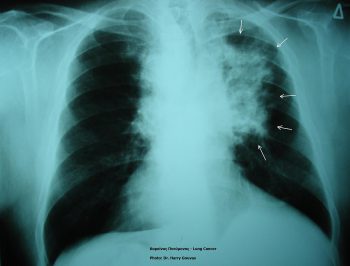

A protein that lets the immune system “see” lung cancer

Posted on July 28, 2022October 24, 2022 by Sciworthy

Personalized cancer treatment is on the rise. Cancer is not just one disease but thousands of different types and subtypes that each respond…

New therapy for non-small cell lung cancer

Posted on July 21, 2022October 24, 2022 by Sciworthy

Scientists at H. Lee Moffitt Cancer Center and Research Institute recently completed a Phase 1 trial for a new therapy for non-small cell…